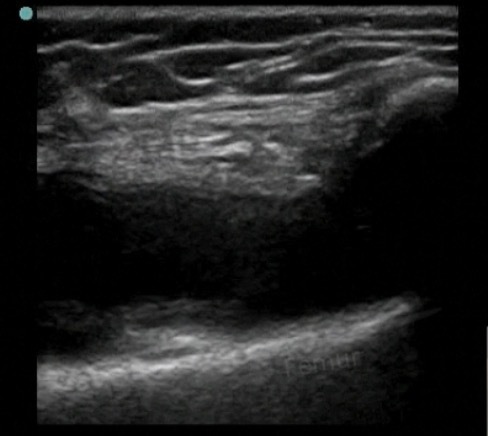

Knee Joint Effusion Image